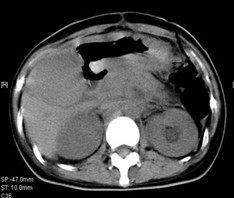

女,40歲,2006年10月底確診為胃腺癌(皮革胃),腹腔淋巴結(jié)轉(zhuǎn)移;2006年11月外科手術(shù)時(shí)見(jiàn)腹腔廣泛轉(zhuǎn)移(粘連),病灶無(wú)法切除(下圖1a,b),預(yù)期生存期低于3個(gè)月;留置(胃)造瘺管。2006年12月開(kāi)始今又生聯(lián)合化療治療,今又生2×1012VP,室溫下自行融化后加入到100ml生理鹽水中,30~40分鐘內(nèi)靜脈滴注完畢,1/次/周,連續(xù)使用6周。今又生給藥三天后靜脈化療。2007年7月外科手術(shù)拔除造瘺管;2007年9月隨訪,患者狀況良好,無(wú)復(fù)發(fā)。

2a 治療前 主動(dòng)脈前方,胃底和脾門(mén)之間見(jiàn)大量結(jié)節(jié)狀淋巴結(jié)

2b 治療后 主動(dòng)脈前方,胃底和脾門(mén)之間淋巴結(jié)大部分消失縮小,脂肪間隙較前清晰